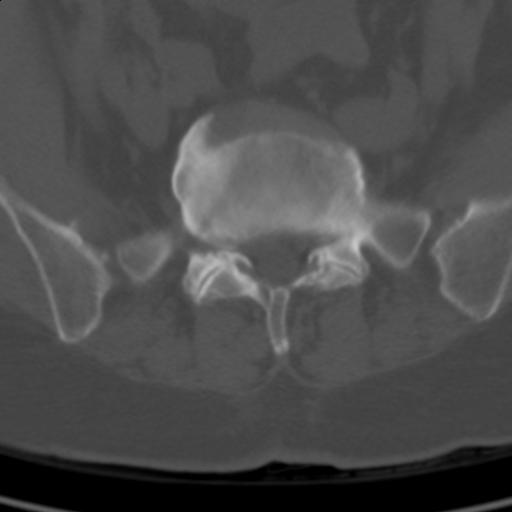

患者;女性;左下肢疼痛。

l5s1显示椎间盘突出,椎体边缘骨质增生,双侧黄韧带钙化。(请上传骨窗)

l5s1显示椎间盘突出,椎体边缘骨质增生,双侧黄韧带钙化 ,两侧椎小关节肥大,关节面硬化,关节间隙变窄,提示:椎小关节综合症

双侧的侧隐窝有狭窄。

我认为应该考虑为:l5s1椎间盘膨出,余(椎小关节退变、黄韧带钙化、椎间孔狭窄)与各位同行无异议。

l5s1显示椎间盘膨出,突出,椎体边缘骨质增生向后压迫硬膜囊,双侧黄韧带钙化,小关节面综合征